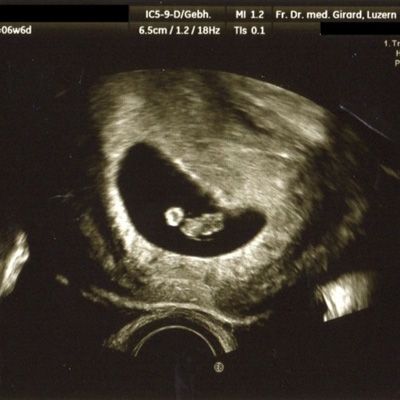

Im ersten Trimester

(12 – 13 SSW)

können wir die Intaktheit und das Alter der Schwangerschaft feststellen. Diese Information ist von grosser Bedeutung, um beispielsweise in der Spät-Schwangerschaft ein allfälliges vermindertes Wachstum des Kindes erkennen zu können. Auch können Mehrlinge mit hoher Sicherheit erfasst oder ausgeschlossen werden. Zudem kann schon in diesem frühen Alter eine Reihe schwerer Fehlbildungen erkannt werden. Mit der Messung der Nackenhaut-Dicke können Hinweise auf eine mögliche Chromosomen-Störung (beispielsweise das Down-Syndrom = Trisomie 21) erfasst werden.